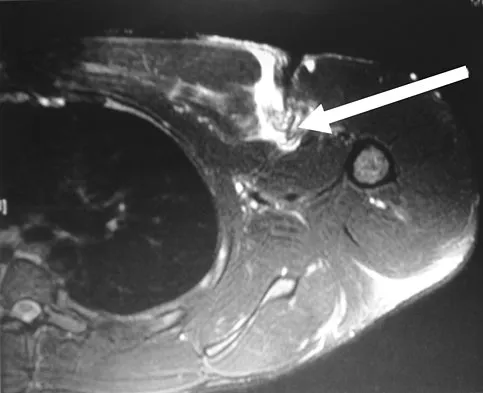

An MRI arthrogram of the elbow is shown in Figure 6. Based on these findings, what is the most likely diagnosis?

Explanation